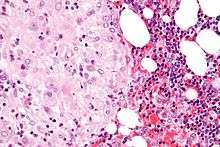

The decidua has a histologically-distinct appearance, displaying large polygonal decidual cells in the stroma. These are enlarged endometrial stromal cells, which resemble epithelium (and are referred to as "epithelioid").

Decidualization includes the process of differentiation of the spindle-shape stromal fibroblasts into the plump secretory decidual cells, which create a pericellular extracellular matrix rich in fibronectin and laminin (similar to epithelial cells).

Its leukocyte population is distinct, with the presence of large endometrial granular leukocytes being predominant, while polynuclear leukocytes and B cells are scant.

The large granular lymphocytes (CD56 bright) are called "uterine NK cells" or "uNK cells" in mice, and "decidual NK cells" or "dNK cells" in humans.

The region of fibrinoid degeneration where trophoblasts meet decidua is called Nitabuch's layer. This layer is absent in placenta accreta.[1]